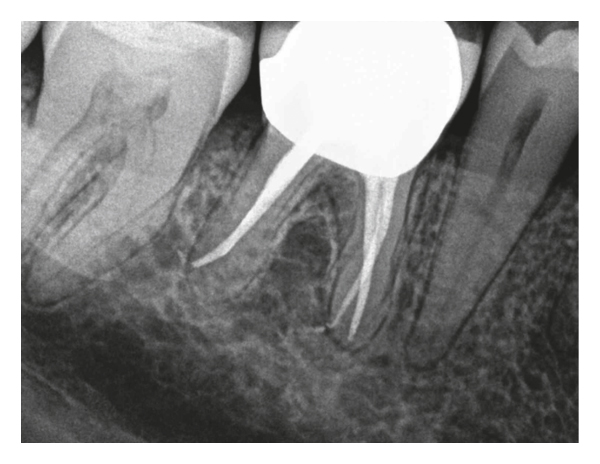

After anesthesia with 4% septocaine with 1 : 100,000 adrenaline (Ubistesin Forte, 3M ESPE, Seefeld, Germany) and rubber dam isolation (Hygenic Dental Dam, Coltene Whaledent, Langenau, Germany), the coronal restoration was removed, and an access cavity was prepared. The pulp chamber was presented with calcification, and no canal orifices could be identified clinically under the dental operating microscope. Ultrasonic preparing was performed in an attempt to locate the canal orifices, but it was not successful. Following that, two GP points were placed and compacted where the orifices of the mesiobuccal and palatal canals were estimated to be (Figure 3(b)). A cotton pellet moistened with sodium hypochlorite was placed in the access cavity, and the tooth was temporarily sealed with 4 mm of Cavit G (3M ESPE, Seefeld, Germany). The patient was referred for limited FOV CBCT of the tooth (Morita 3D Accuitomo 170, J. Morita MFG Corp., Irvine, CA, USA). The axial view of the CBCT revealed that the palatal canal orifice was located at the GP placed on the palatal position whereas the mesiobuccal canal was located buccally to where the respective GP point was placed (Figures 3(c) and 3(d)). At the second visit, temporary filling materials were removed, and ultrasonic preparing was performed according to the information from the CBCT. By use of a microopener No. 10/.04 (Dentsply Maillefer, Tulsa, OK, USA), the palatal canal orifice was found and confirmed using an apex locator (Root ZX II, J. Morita MFG Corp., Irvine, CA, USA). The orifices of the mesiobuccal and distobuccal canals could not be located. Root canal preparation of the palatal canal was carried out using an endodontic rotary instrumentation system (Race, FKG Dentaire SA, La Chaux-de-Fonds, Switzerland) up to a 40/0.4 file. Sodium hypochlorite 2.5% was used for copious irrigation. The canal was filled with GP and epoxy sealer (AH Plus, Dentsply Maillefer, Tulsa, OK, USA) using warm vertical compaction. Preparation of a post was made on the palatal canal. The access cavity was temporarily sealed with cotton pellet and Cavit G, and a postoperative radiograph was taken (Figure 3(e)). The tooth was followed up for a month and remained asymptomatic. After that, the patient was referred back to the prosthodontist.